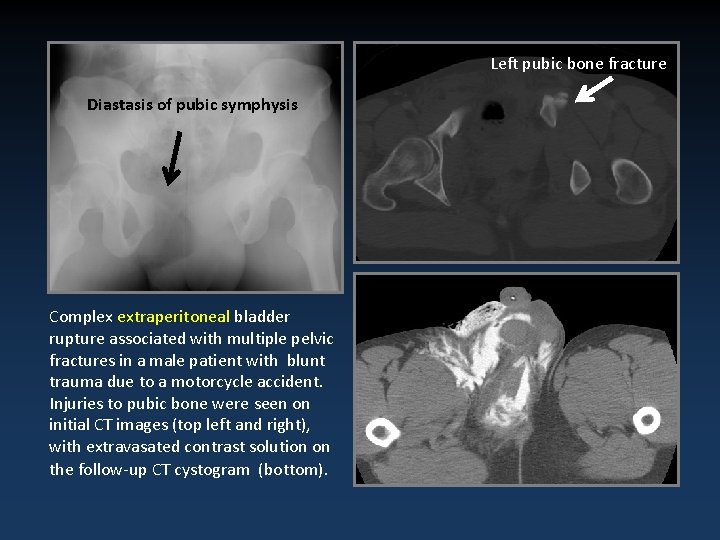

Left pubic bone fracture Diastasis of pubic symphysis Complex extraperitoneal bladder rupture associated with multiple pelvic fractures in a male patient with blunt trauma due to a motorcycle accident. Injuries to pubic bone were seen on initial CT images (top left and right), with extravasated contrast solution on the follow-up CT cystogram (bottom).